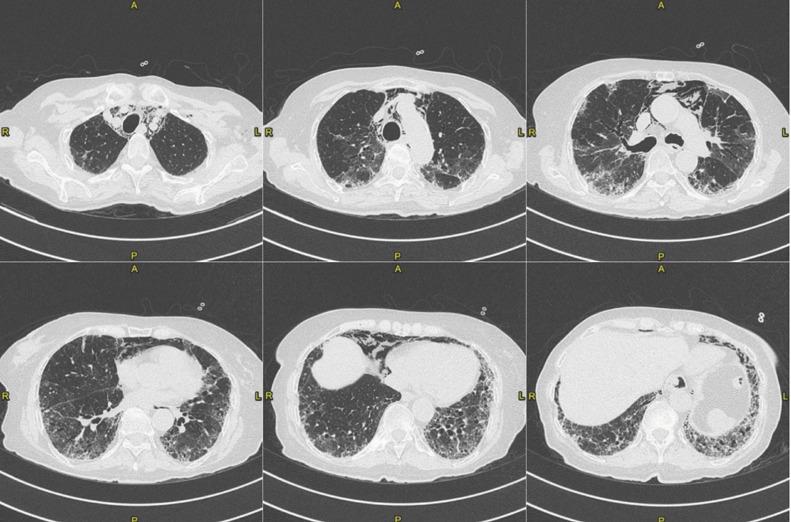

Platypnea-Orthodeoxia Syndrome (POS) is a clinical entity defined as positional dyspnoea (platypnea) and arterial desaturation (orthodeoxia) that occurs when sitting or standing up and usually resolves by lying down. Up to April 25th 2021, eleven cases of POS after SARS-CoV-2 pneumonia have been reported on Pubmed. Accordingly, SARS-CoV-2 infection may be considered as an emergent cause of POS due to an increase in ventilation/perfusion (V/Q) mismatch. In this article we provide an update on the patient with POS after fibrotic evolution of SARS-CoV-2 interstitial pneumonia, which we previously reported and we discuss the case reports of POS due to SARS-CoV-2 infection.

体位性呼吸困难-低氧血症综合征(POS)是一种临床病症,定义为当坐立或站立时出现呼吸困难(体位性呼吸困难)和动脉血氧饱和度降低(低氧血症),而当躺下时通常会缓解。截至 2021 年 4 月 25 日,在 Pubmed 上已报告了 11 例 SARS-CoV-2 肺炎后 POS 病例。因此,由于通气/血流(V/Q)不匹配增加,SARS-CoV-2 感染可被视为 POS 的一个新出现病因。在本文中,我们对先前报道的纤维化演变后的 SARS-CoV-2 间质性肺炎后出现 POS 的患者进行了更新,并讨论了因 SARS-CoV-2 感染而出现 POS 的病例报告。